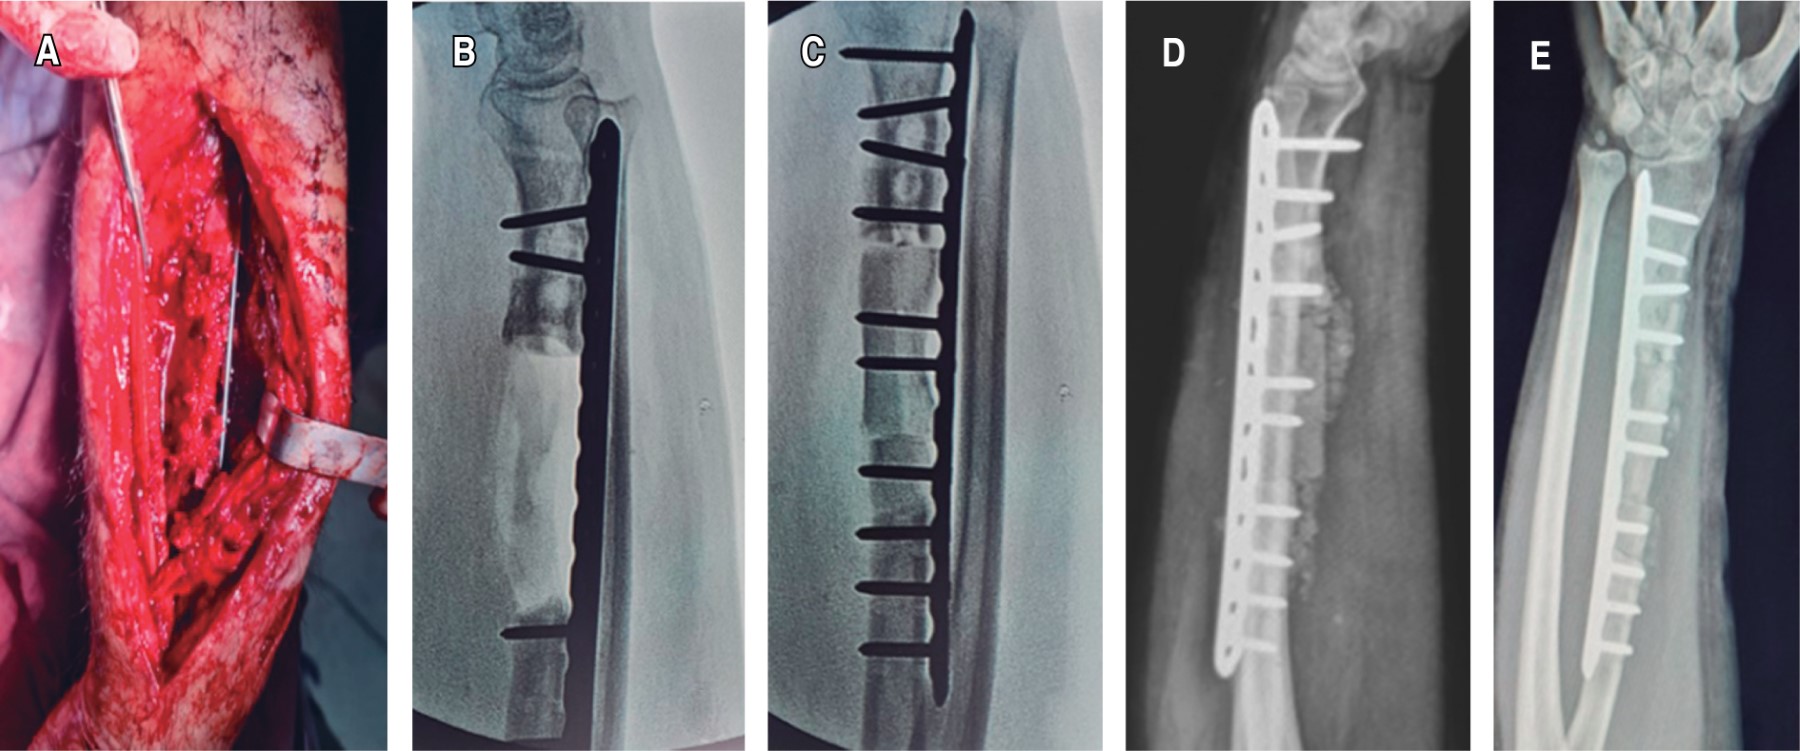

Masculino de 30 años, comerciante, diabético tipo 2 descontrolado como comorbilidad, con antecedente de un mes atrás haber sufrido fractura de radio izquierdo secundaria a caída en motocicleta y ser tratado mediante osteosíntesis con placa de compresión dinámica (DCP, por sus siglas en inglés) de 3.5 de radio. Padecimiento de 15 días de evolución caracterizado por dolor en antebrazo izquierdo EVA (escala visual analógica) 3/10 que se tornó progresivo, presencia de fístula con exudado purulento (Figura 1). Es tratado en un inicio con toma de cultivo e inmovilización y posteriormente con primer tiempo quirúrgico, donde se practica aseo quirúrgico, retiro de material de osteosíntesis y estabilización con fijador externo.

En las radiografías iniciales se aprecia foco de pseudoartrosis séptica, aumento de volumen de tejidos blandos, con pérdida ósea menor de 1 cm y luxación de articulación radiocubital distal. El segundo tiempo quirúrgico, ya con cultivo positivo para Pseudomonas aeruginosa y tratamiento intravenoso de acuerdo con antibiograma con ciprofloxacino y amikacina por 21 días, se procede a realizar nuevo aseo y debridación, con resección de tejido óseo desvitalizado y aplicación de la técnica de Masquelet fase 1, con cemento medicado con gentamicina y vancomicina (Figura 2).